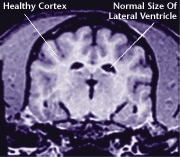

Healthy Older Brain

MRI scans show loss of brain tissue in affected dogs.

Note: MRI scans are not harmful to dogs.